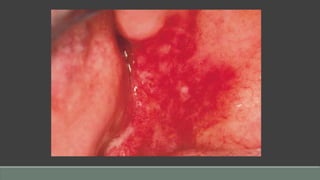

Pyogenic Granuloma

Etiology

• A reactive hyperplasia of capillaries and fibroblasts

• Related to chronic, persistent trauma or irritation (eg, calculus or foreign body)

• Misnomer—neither pyogenic nor granulomatous

◦ My advice 🡪 Capillary Lobular Hemangioma !

Clinical Presentation

• Occurs at any age, but usually in children, young adults, and women

• Red, lobular to smoothly contoured appearance

• When ulcerated, a yellow fibrinous exudate covers the lesion.

• Sessile to pedunculated commonly on gingiva, but also on areas that are traumatized (eg,

lower lip, buccal mucosa)

• Bleeds easily but is painless

Diagnosis

• History of gradual to rapid onset

• Identification of a stimulus or causative factor (eg, trauma, physical irritant)

• Histologic evaluation

Differential Diagnosis

• Peripheral giant cell granuloma

• Peripheral ossifying fibroma

• Metastatic tumor

• Kaposi’s sarcoma

• Vascular malformation

Prognosis

• Excellent

• Recurrence occasional